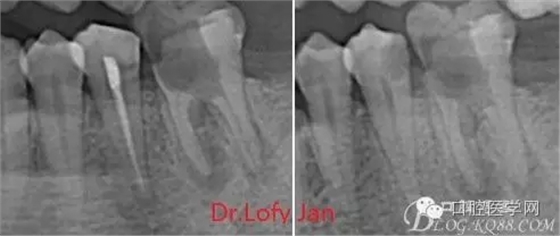

根管治療術(shù)是牙體牙髓疾病治療中最復(fù)雜和最關(guān)鍵的治療項(xiàng)目。根管充填材料抵達(dá)根尖、并能嚴(yán)密堵塞根尖孔,是確保根管治療效果的關(guān)鍵指標(biāo)。為了保證根管充填到位,醫(yī)生需要在術(shù)前照牙片以了解牙根根管的數(shù)量、彎曲程度和長(zhǎng)度,在術(shù)中有時(shí)需要插針照牙片來精確測(cè)量根管長(zhǎng)度,術(shù)后必須照牙片以確定是否根管充填到位,如果欠填或超填,就需要重新充填、重新照牙片確認(rèn),直到根管充填到位。所以,在患者接受根管治療時(shí)有時(shí)會(huì)反復(fù)照牙片。

《數(shù)字化根尖片、曲面斷層片、CBCT測(cè)量牙齒長(zhǎng)度準(zhǔn)確性的比較研究》文中顯示:平行投照數(shù)字化根尖片影像長(zhǎng)度和牙齒實(shí)際長(zhǎng)度之間無顯著性差異(P0.05);數(shù)字化曲面斷層片影像長(zhǎng)度和牙齒實(shí)際長(zhǎng)度之間有顯著性差異(P0.05),平均失真率為17.05%。CBCT冠狀面測(cè)量結(jié)果中除上頜前磨牙區(qū)、下頜前磨牙區(qū)與真實(shí)長(zhǎng)度差異無統(tǒng)計(jì)學(xué)意義(P0.05)外,其余6個(gè)分區(qū)差異均有統(tǒng)計(jì)學(xué)意義(P0.05);矢狀面測(cè)量結(jié)果中上頜磨牙區(qū)、下頜磨牙區(qū)、下頜前磨牙區(qū)、下頜尖牙區(qū)、下頜前牙區(qū)與真實(shí)長(zhǎng)度比較差異均有統(tǒng)計(jì)學(xué)意義(P0.05)。結(jié)論平行投照數(shù)字化根尖片較曲面斷層片和CBCT能更加精確地反映牙齒的真實(shí)長(zhǎng)度。

病例分析:曲面斷層片在x線輔助診斷與檢查中目前大多數(shù)文獻(xiàn)和著作都建議只能作為初診拍片檢查手段,不能作為終末疾病的確診與手術(shù)療效的評(píng)價(jià)指標(biāo),臨床大部分中小型門診都因?yàn)樵O(shè)備不齊全導(dǎo)致信息偏差很大。